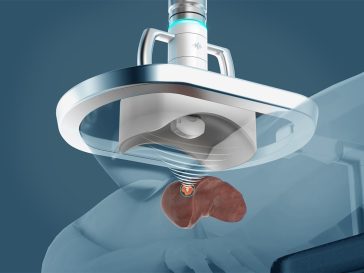

Revolutionary drug testing techniques: Vascularized organ-on-a-chip glimpses the future

Vascularized Organ-on-a-Chip Systems: Revolutionizing Medical Research Medical research is evolving rapidly, and thanks to the advancements in biomedical engineering, a groundbreaking development is currently set to revolutionize the way we approach drug testing and disease modeling. Organ-on-a-chip technology mimics human organs on a microscale by cultivating cells in a controlled microenvironment that simulates the 3D […] More